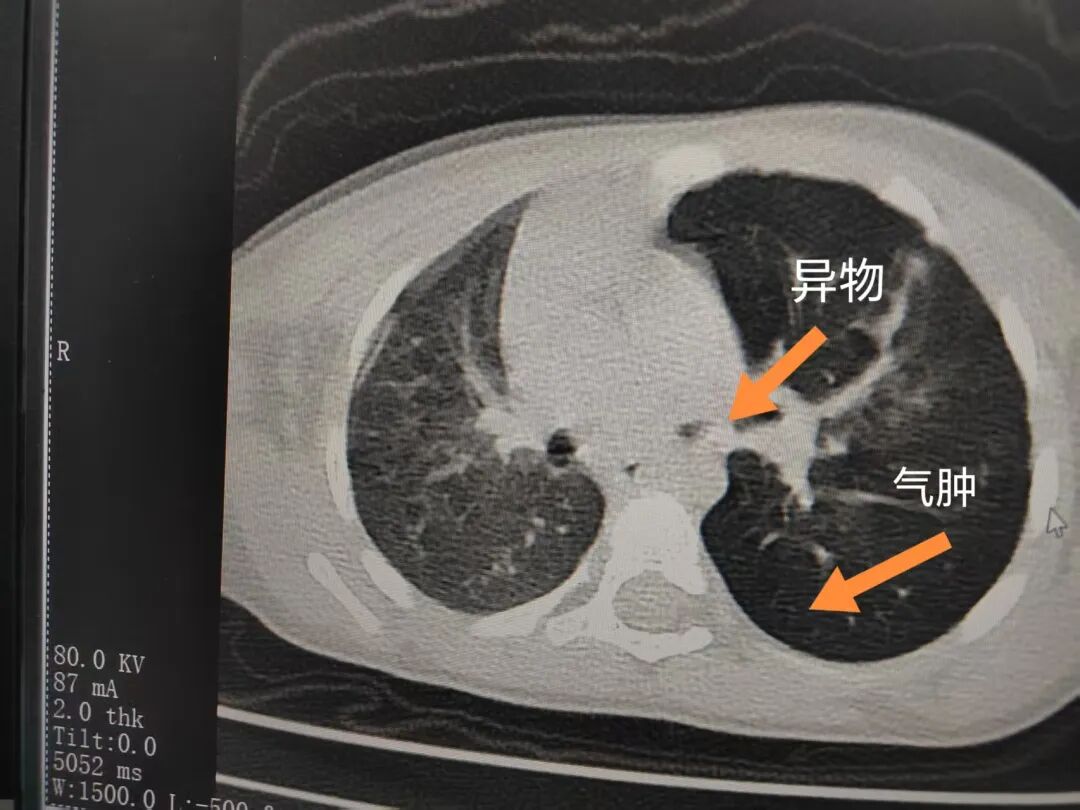

三天后(11月13日),趙寶出現(xiàn)高熱、咳喘加重,家長(zhǎng)著急了,再次帶他來(lái)到醫(yī)院。CT檢查顯示左肺過(guò)度充氣,左肺上下葉支氣管主干見不規(guī)則高密度影,左肺上葉可見大片狀密度增高影,縱隔窗實(shí)變,提示為“左側(cè)支氣管內(nèi)異物并繼發(fā)性改變,左肺上葉舌段肺膨脹不全”。

市二院小兒呼吸內(nèi)科副主任楊亞娟介紹,異物誤入氣道可能導(dǎo)致氣道阻塞,嚴(yán)重時(shí)可引發(fā)窒息,甚至危及生命。若異物進(jìn)入支氣管,造成不完全堵塞,可引起阻塞性肺氣腫;如完全堵塞支氣管,則可能導(dǎo)致肺組織萎縮,形成肺不張。此外,若異物存留時(shí)間較長(zhǎng),或?yàn)橹参镄援愇铮菀缀喜⒓?xì)菌感染,產(chǎn)生膿性分泌物,進(jìn)而發(fā)展為肺炎。她強(qiáng)調(diào),盡早診斷并取出異物,是減少并發(fā)癥、降低病死率的關(guān)鍵。